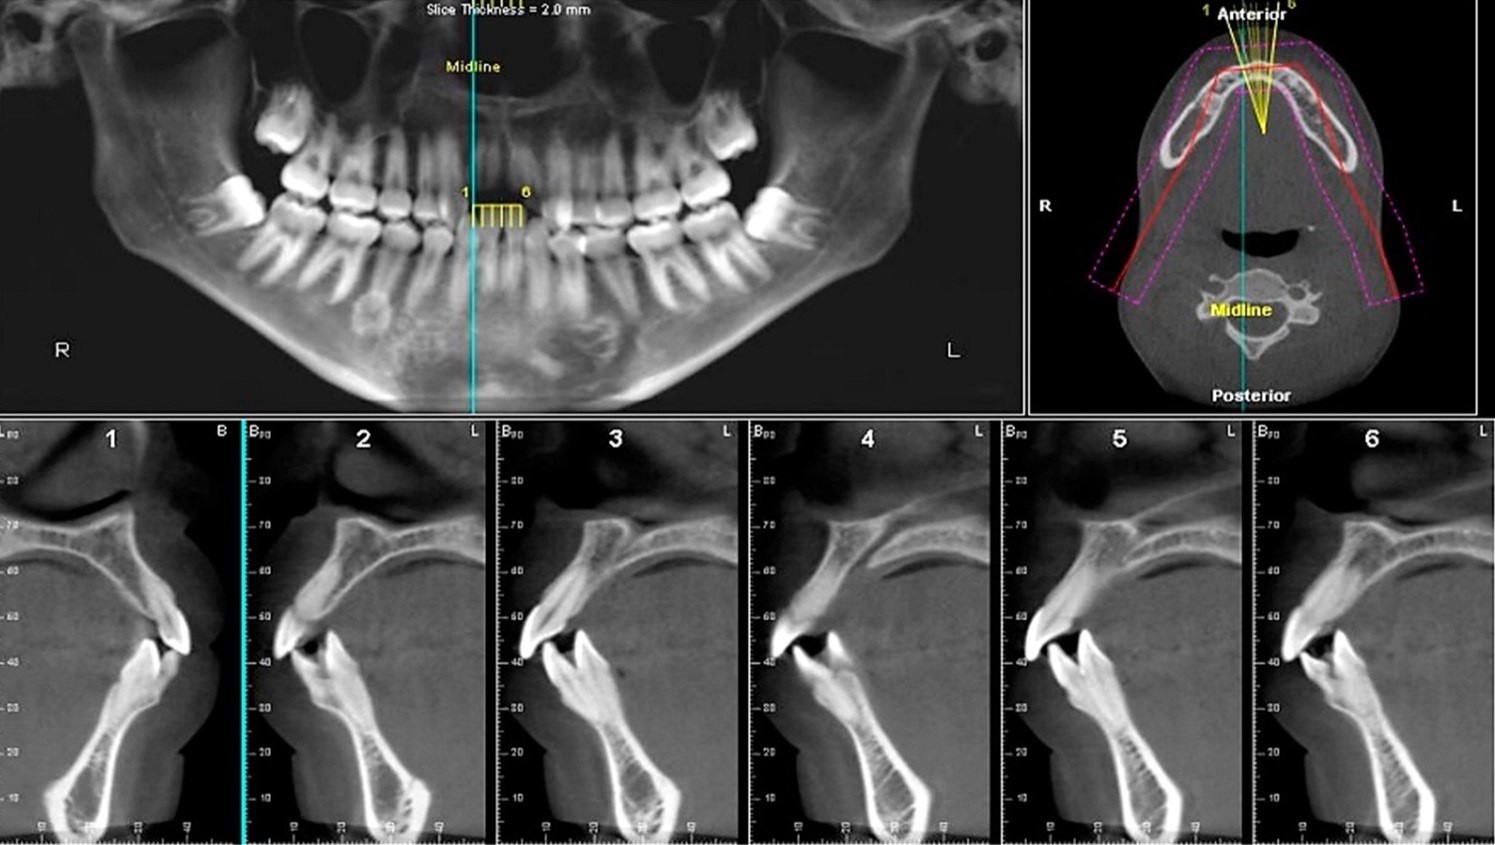

A radiology report can be provided with Fusion Radiology whether a CBCT scan or OPG x-ray. Our radiologist will review the DICOM file from your patient's CBCT scan, interpret the radiographs and create a comprehensive report covering the area of interest and pathology. All of our radiology reports are all in digital format, which will enable you to instantly download a PDF version.

Get diagnostic CBCT reports directly from NHS Dental Radiologists.